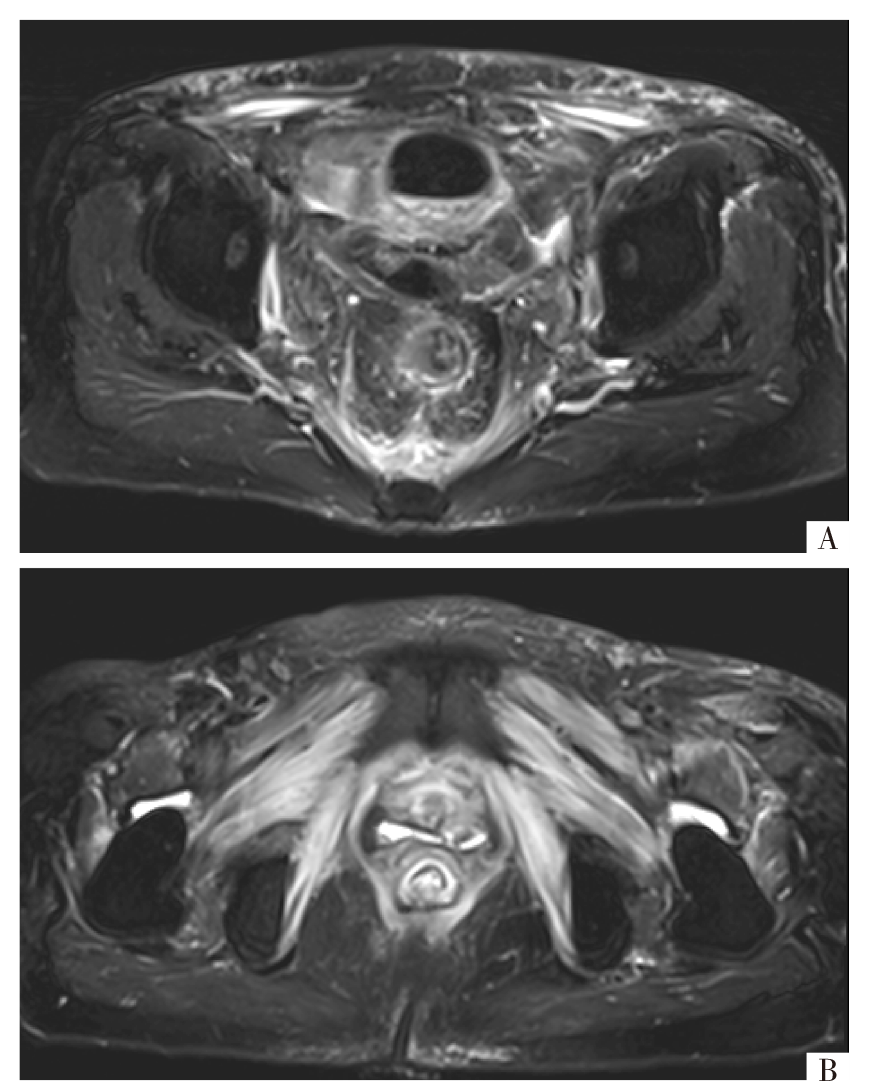

宫颈癌的发病率高居妇科恶性肿瘤之首,目前手术仍然是早期宫颈癌有效的治疗方法。但宫颈癌具有较高的复发率和远处转移能力,晚期预后差,治疗选择有限。报告1例宫颈癌根治术和放化疗联合治疗后仍复发,出现膀胱阴道瘘和直肠阴道瘘并发严重感染的患者,经卡度尼利单抗单药及联合化疗治疗取得了生存获益,旨在为复发性宫颈癌的治疗提供新思路。

The incidence rate of cervical cancer is the highest among gynecological malignancies. At present, surgery is still an effective treatment for early-stage cervical cancer, but cervical cancer has a high recurrence rate and distant metastasis, poor prognosis in advanced stages, and limited treatment options. This article focuses on a case with recurrence of cervical cancer despite radical hysterectomy and combined chemotherapy and radiotherapy, who developed vesicovaginal fistula and rectovaginal fistula with severe infection, and achieved a survival benefit by treatment with cadonilimab monotherapy and combination chemotherapy. It aims to provide new ideas for the treatment of recurrent cervical cancer.